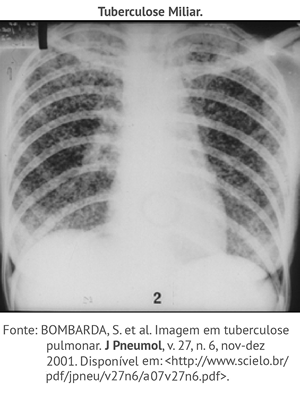

Clique nos números abaixo e observe as imagens radiológicas referentes a pneumonia TB, TB miliar e derrame pleural.